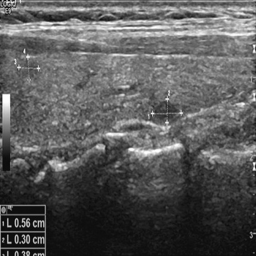

To evaluate the effectiveness of the proposed segmentation framework, we conduct ablation and comparative experiments on two publicly available thyroid ultrasound datasets: TN3K Gong et al. (2021) and DDTI Pedraza et al. (2015). The TN3K dataset consists of 3,494 high-resolution thyroid nodule images, following a standardized clinical split protocol with 2,879 images designated for training and 614 for testing. For the DDTI dataset, which contains 637 thyroid ultrasound scans, the data was randomly split into training and testing sets at a 4:1 ratio. Additionally, 10-fold cross-validation was applied to address the challenge of limited data while ensuring statistical reliability.

Notably, in both datasets, the ground truth annotation of thyroid nodules in ultrasound images for metrics was performed by experienced radiologists, while the point annotation was carried out by less-experienced senior medical students to simulate a real-world weakly supervised learning scenario.